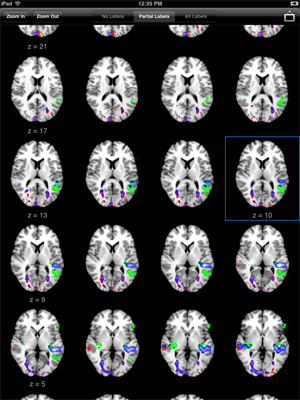

Lightbox

Lightbox Display. Rotate the iPad into portrait orientation to display a lightbox layout of slices. Use one finger to scroll up and down throughout the slices. The current slice is indicated with a highlighted border.

Tap Zoom In/Out to change the number of columns displayed. Select Partial Labels to show labels only in the first column and selected slice. Tap the picture icon to make a screen capture which is saved to the Photos app.